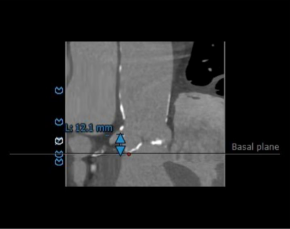

2.术前CT影像评估显示:左冠开口高度为12.1mm,左冠瓣瓣叶长度为15.2mm,冠脉内多发钙化,存在冠脉阻挡风险。

左右冠开口高度可,未见冗长瓣叶,冠脉多发钙化,依据瓦氏窦宽度和瓣叶长度预估右冠风险较小,左冠存在堵塞风险。